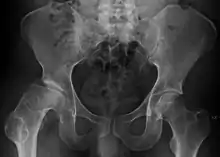

Radiograph of a person with Legg–Calvé–Perthes disease